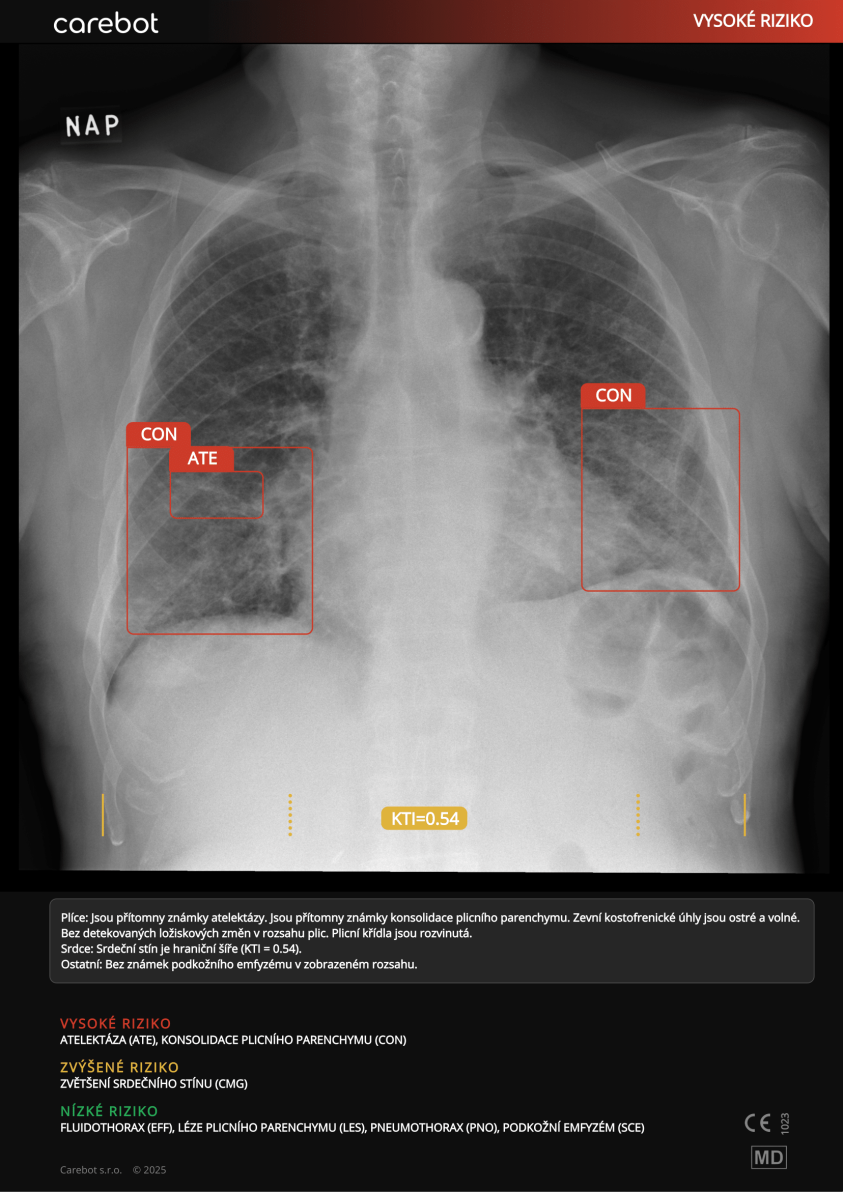

Startup Carebot získal evropskou certifikaci zdravotnického prostředku MDR pro rozšířeného asistenta pro čtení snímků obrazových vyšetření s využitím umělé inteligence. Po produktu s názvem Carebot AI CXR, který analyzuje rentgenové snímky hrudníku, vyvinul nový Horizon by Carebot. Ten v sobě kombinuje sedm nástrojů s umělou inteligencí: vedle analýzy rentgenových snímků hrudníku také detekci kostních fraktur, určení kostního věku a měření páteřních deformací, specializované aplikace pro CT hlavy a CT plic i podporu radiologů při hodnocení mamografických snímků.

Ke každému snímku dostane lékař k dispozici strojové textové hodnocení, které lze použít jako základ lékařské zprávy.